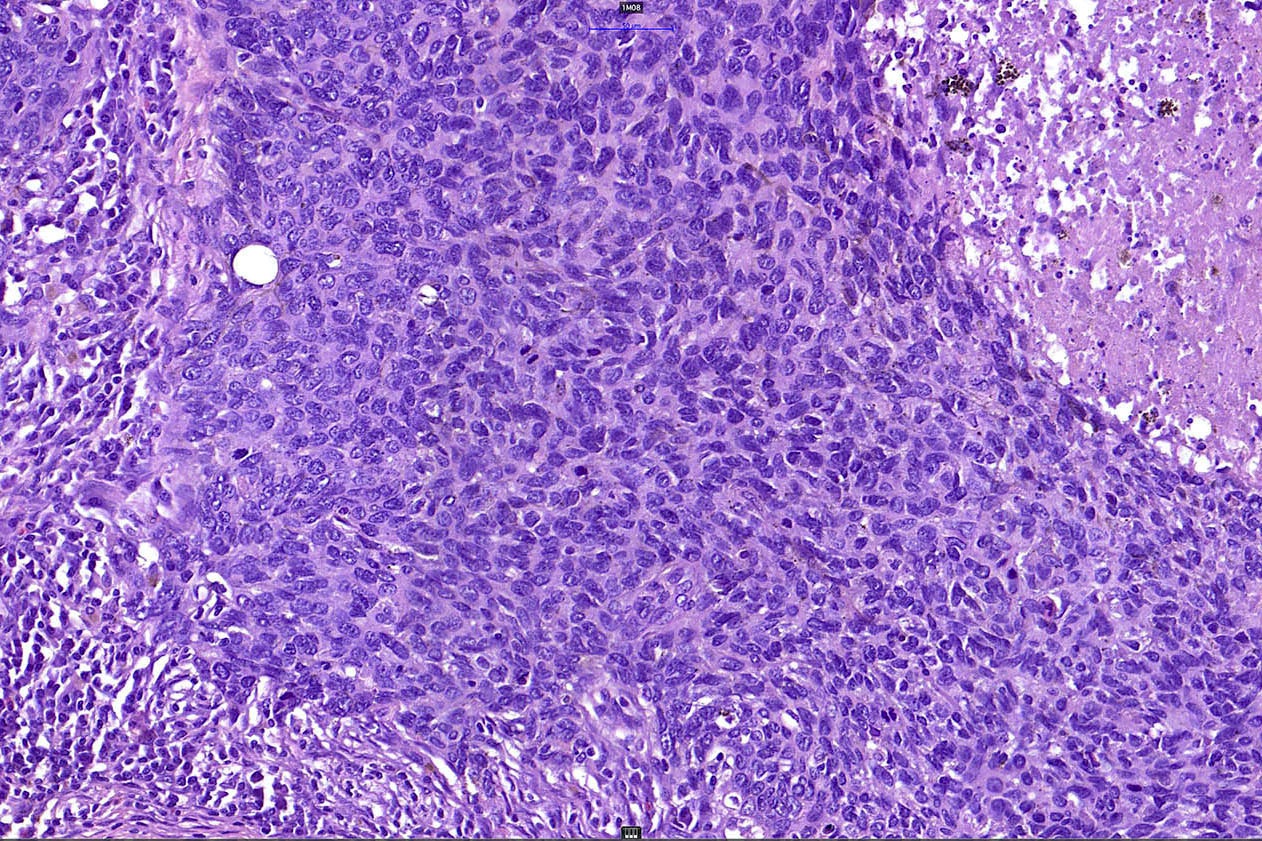

Common variants (Calonje: McKee's Pathology of the Skin, 5th Edition, 2019)

- Micronodular BCC

- Small basaloid nests

- Peripheral palisading less prominent

- Retraction artifact usually absent

- Can diffusely infiltrate the dermis and extend into the subcutis

- Basosquamous (metatypical) BCC

- Biphasic tumor

- Foci of neoplastic squamous differentiation

Microscopic (histologic) images

Contributed by Antonina Kalmykova, M.D., Phillip H. McKee, M.D., Sate Hamza, M.D., Eduardo Calonje, M.D.,

Wayne Grayson, M.B.Ch.B., Ph.D., James Sampson, M.B.B.S., M.Sc. and Assia Bassarova, M.D., Ph.D.